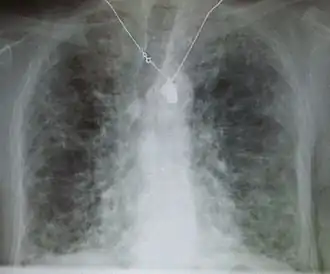

![]() | |

| End-stage pulmonary fibrosis of unknown origin, taken from an autopsy | |